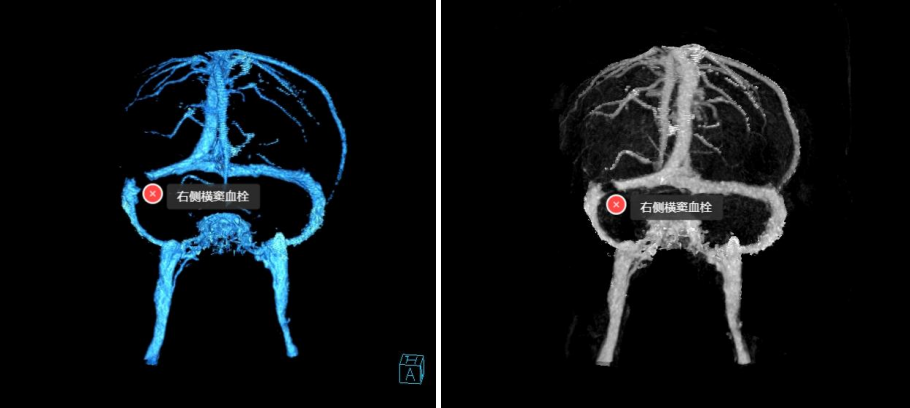

案例2:患者男,53岁,一过性意识丧失12小时。行MRV检查,不排除外右侧横窦静脉血栓形成,建议行CTV检查。

图3(左)为颅底静脉系统解剖示意图,图3(右)为脑静脉CTV后处理的最大密度(MIP)图像,红色箭头表示双侧横窦,图(右)可清晰显示右侧横窦内充盈缺损,提示静脉窦血栓形成。

图4为脑静脉CTV后处理的容积再现(VR)图像,可清晰显示右侧横窦内充盈缺损,提示静脉窦血栓形成。